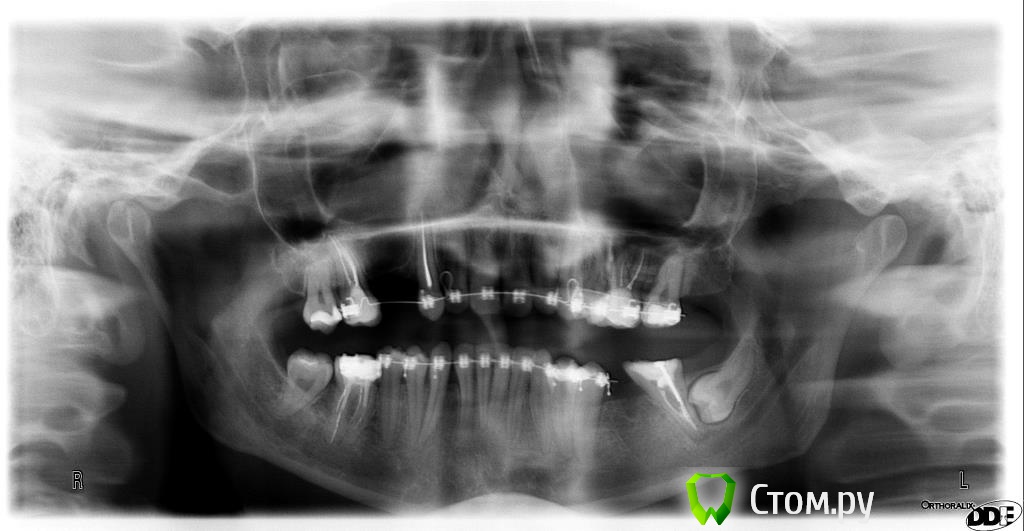

pupsenok Опубликовано 13 декабря, 2013 Поделиться Опубликовано 13 декабря, 2013 (изменено) Добрый день уважаемые врачи!Вопрос на повестке для стоит такой: заканчиваю лечение брекетами, пора приступать к протезированиюэ.Сходила на пару консультаций и тут возникли разногласия: - кто то говорит о мостах, мотивируя долгоиграющую еще возню с имплантами и синуслифтингом, да и последствиями непредсказуемы, - кто то пропрочит импланты, ибо это современно,эстетично и вообще все будет хорошо.Прошу Вашего профессионального вывода и аргументов, ибо решать вопрос надо, и надо как то определится в ближайшее время, пока обратно зубья не полезли)Прилагаю два снимка, нынешний ( за качество извиняюсь), и что было ( может будет интересно).Большое спасибо заранее, за уделенное мне время! Изменено 13 декабря, 2013 пользователем pupsenok Ссылка на комментарий

Igor3252 Опубликовано 15 декабря, 2013 Поделиться Опубликовано 15 декабря, 2013 Мосты- время революции . Судя п0 последнему снимку-14,15 имплант . Либо один между 14-15 и на него две коронки. Нужно смотреть расстояние по к/т Нижнюю левую 8 убрать однозначно .. ( минут 30 ) 36 имплант .. И не нужны Вам никакие мосты . Это сугубо мое IMHO Ссылка на комментарий